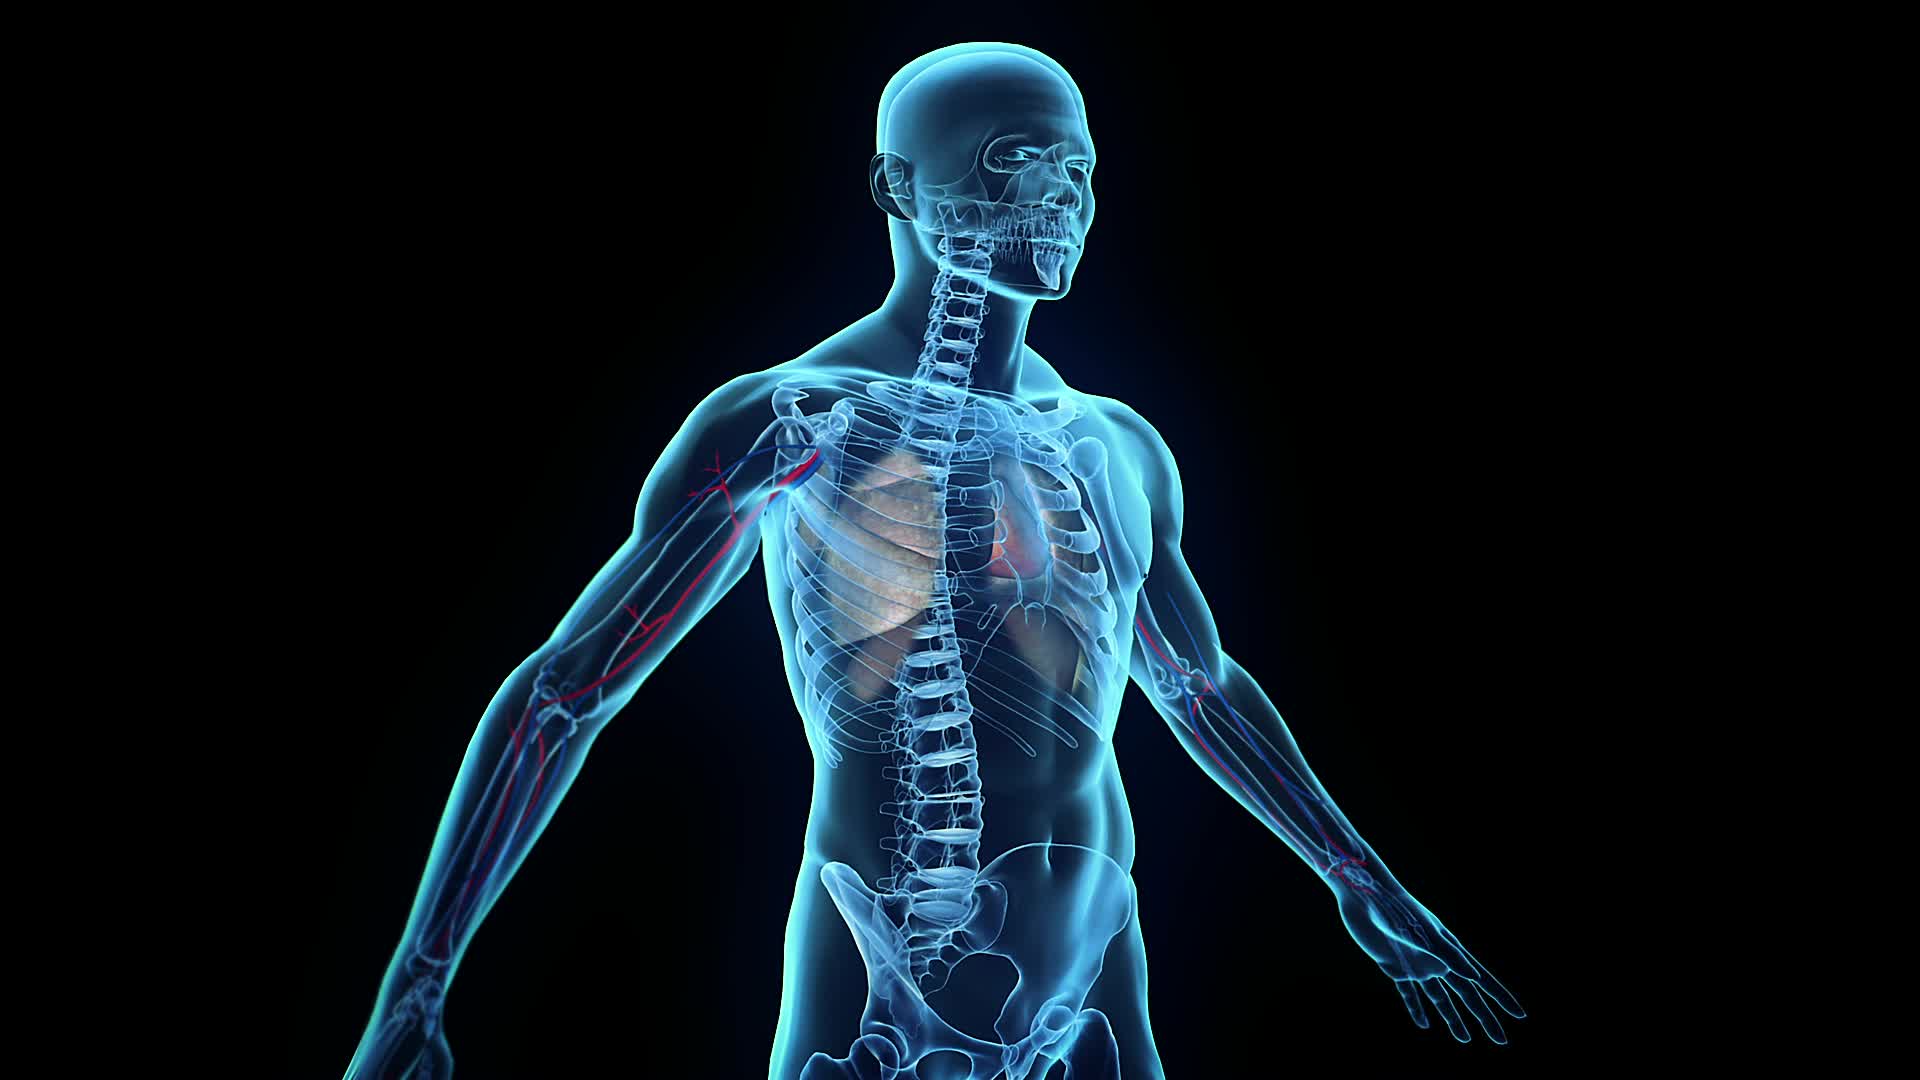

Radiology Wallpapers - Wallpaper Cave

wallpapercave.comradiology wallpaper wallpapers footage organe pond5 innere stock backgrounds desktop wallpapersafari full

wallpapercave.comradiology wallpaper wallpapers footage organe pond5 innere stock backgrounds desktop wallpapersafari full

Fisioterapia Traumatológica - Sananova

sananova.esX-ray Wallpapers - Wallpaper Cave

sananova.esX-ray Wallpapers - Wallpaper Cave

wallpapercave.comwallpaper ray wallpapers radiology bone xray background desktop hd cracking knuckle mystery cracks math breakdown needs bit building first getty

wallpapercave.comwallpaper ray wallpapers radiology bone xray background desktop hd cracking knuckle mystery cracks math breakdown needs bit building first getty

theposterdb.comMedical Arts Radiology | MRI Commercial

theposterdb.comMedical Arts Radiology | MRI Commercial

www.pinterest.comradiology mri radiologic technologist radiologist imaging geometric blue radiologists direct

www.pinterest.comradiology mri radiologic technologist radiologist imaging geometric blue radiologists direct

www.pxfuel.comRadyoloji, Radyografi HD Duvar Kağıdı | Pxfuel

www.pxfuel.comRadyoloji, Radyografi HD Duvar Kağıdı | Pxfuel